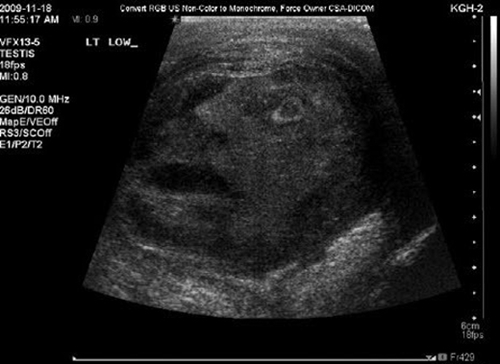

해당 사진은 고환암을 앓고 있는 45세 남성의 고환을 찍은 초음파 사진이며 사진 속 암 덩이에는 눈과 입을 크게 벌리고 있는 악마의 형상이 언뜻 보인다.

이 사진은 캐나다의 온타리오 퀸스 대학의 나지 토우 박사와 그레그 로버츠 박사가 발견한 것으로 지난 달 28일자 미국 워싱턴 DC의 고등교육소식지(The Chronicle of Higher Education)에 '고환암의 얼굴'이라는 제목으로 게재된 이후 온라인으로 확산됐다.

그러나 학자들은 토론 끝에 이 영상이 우연히 촬영된 것이지 어떤 신성한 메시지가 드러난 것은 아니라고 결론냈으며 해당 고환암 환자 역시 조직검사 결과 음성인 것으로 알려졌다.